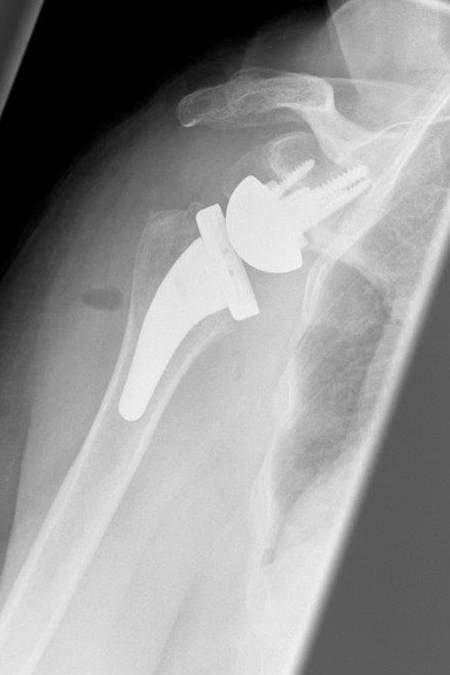

Deutliche rechtsseitige Omarthrose (Schultergelenksverschleiß) mit dorsalem knöchernem Pfannendefekt in der dreidimensionalen präoperativen Planung. Operative Behandlung mit einem Knochenaufbau (BIO RSA) über den körpereignen Knochen aus dem Oberarmkopf und einem Inversen künstlichen Schultergelenk mit kurzem Schaft.

86-jährige Patientin mit einer fortgeschrittenen Arthrose des rechten Schultergelenks und deutlicher Bewegungseinschränkung vor der Operation. In den präoperativen Planungs-CT-Bildern deutliche Deformierung des Oberarmkopfes durch die arthrosebedingten Randanbauten erkennbar.  2,5 Monate nach Operation und Rehabilitation bereits gutes alltagstaugliches Ergebnis nach Implantation einer Inversen Prothese.

Deutliche Knochenausziehung am Oberarmkopf vorn bei Arthrose

Kontrollbild nach Implantation einer Inversen Prothese